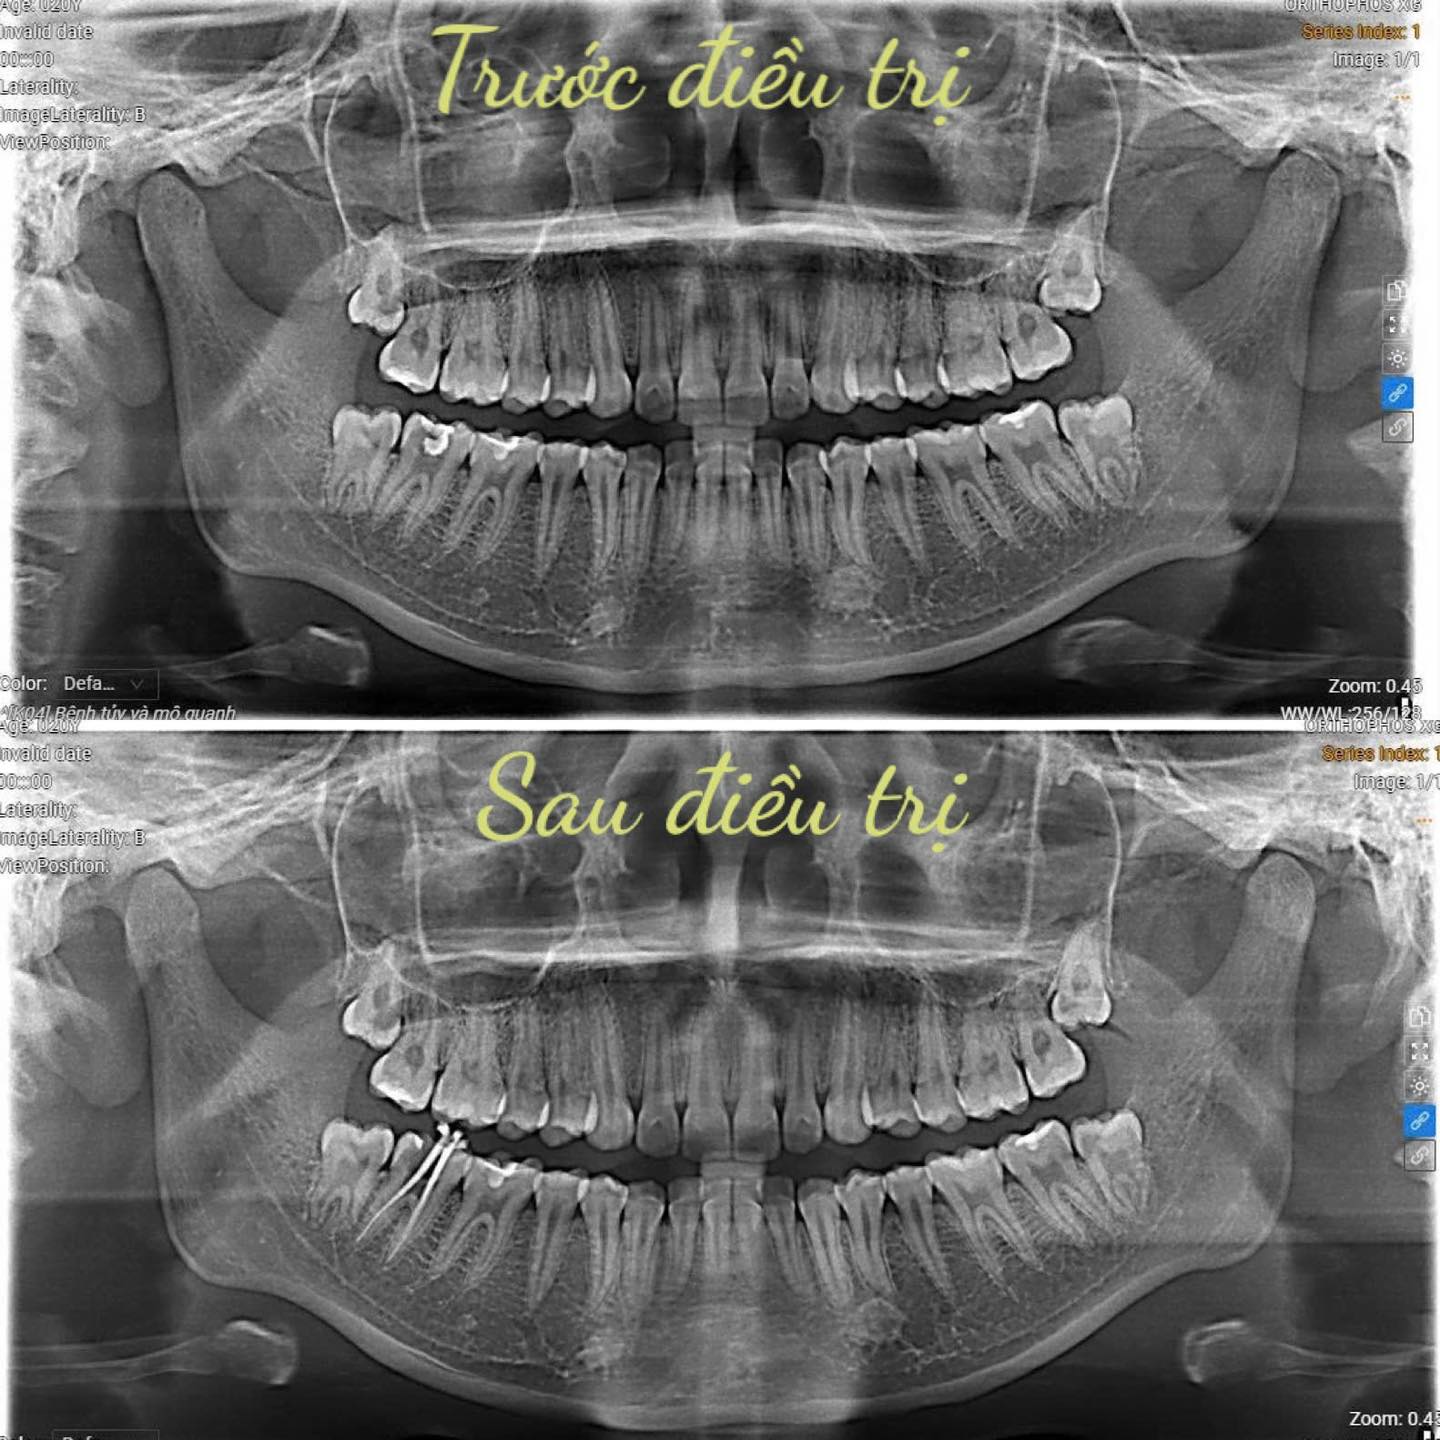

Tại Khoa Răng Hàm Mặt Bệnh viện Trường Đại học Kỹ thuật Y tế Hải Dương, quy trình điều trị tủy được thực hiện bởi đội ngũ bác sĩ giàu kinh nghiệm, kết hợp hệ thống thiết bị hiện đại, đảm bảo an toàn-nhẹ nhàng – hiệu quả.